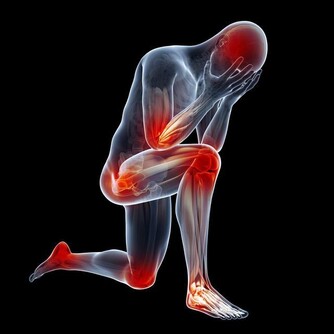

說起腰痛,可能任何一個成年人都遇到過。是否一提起腰痛,您的第一個反應就是「是不是得了腰椎間盤突出症」?一定程度上說,「腰痛」和「腰椎間盤突出」都很常見。據研究,超過50 歲的人100% 出現腰椎間盤退變。同時,超過50 歲的人也幾乎人人都腰痛過。

腰椎間盤突出確實常見,腰痛也常見,但是,腰椎間盤突出卻並不是腰痛的主要原因。事實上,腰痛患者符合腰椎間盤突出症診斷標準的比例只有3%~8%。 那麼,大多數人的腰痛是什麼原因引起的呢?該怎麼治療,或者有沒有什麼方法預防呢? 錯誤姿勢是罪魁禍首 我們先來看看腰痛的原因。 日常生活和工作中最容易導致腰痛的原因是彎腰抬物,如工人搬運重物、婦女端放洗衣盆等。在這些情況中,如果不注意姿勢,尤其是平日難得有機會進行重體力勞動的腦力勞動者,或缺乏鍛煉的家庭婦女,很容易造成腰痛。

彎腰抬物如何造成腰痛呢? 通常我們拾取地面重物最常用的方法是直膝彎腰,因為這麼做重心上下移動距離最小,人體消耗能量也最小。 但要注意,這種姿勢雖然做功較少,但是基本上都要靠腰背肌肉發力,腰背肌肉韌帶負擔是較大的,容易造成腰骶部肌肉、韌帶損傷。久而久之,腰背部相對薄弱的肌肉和韌帶就會造成損傷,出現疼痛。 所以說,腰痛的主要病理因素不在腰椎間盤,而在腰背肌肉和韌帶的損傷。三個動作,趕走腰痛! 1.橋式運動 採取仰臥位,雙膝屈曲併攏置於床上,抬起臀部,頭部和肩部置於床面整個人形成拱橋狀故得名橋式運動。